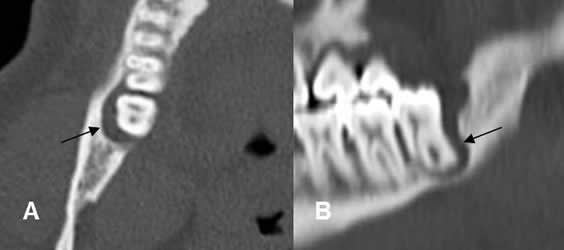

Fig 38. Enfermedad endodental.

A: TAC axial, B: TAC reconstrucción coronal y C: TAC reconstrucción sagital.

Reemplazo de la pulpa de los dientes, por caries extendidas internamente. (Flechas gruesas). Se encuentra perilucencia periapical, por enfermedad endodental.(Flechas delgadas).